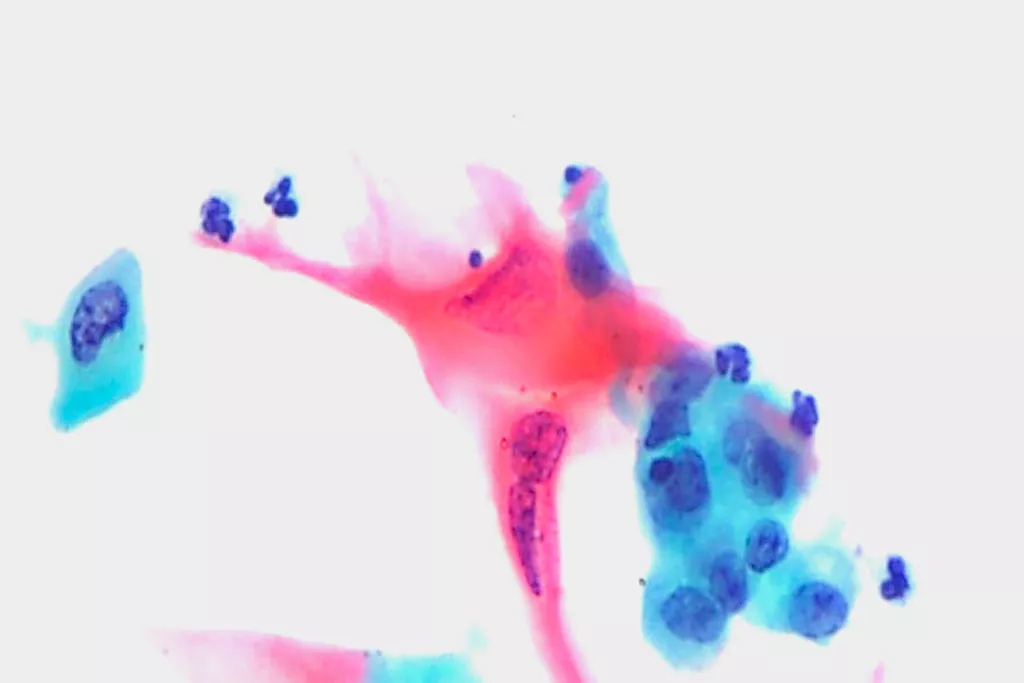

Image Gallery9

9. Images received from Cytopathology Department, Llandough Hospital, Wales

Visualisation

Significantly more effective than conventional Pap smear for the detection of Low-grade Squamous Intraepithelial Lesion (LSIL) and more severe lesions (HSIL).2

Improved ability to detect glandular disease compared to conventional Pap.2